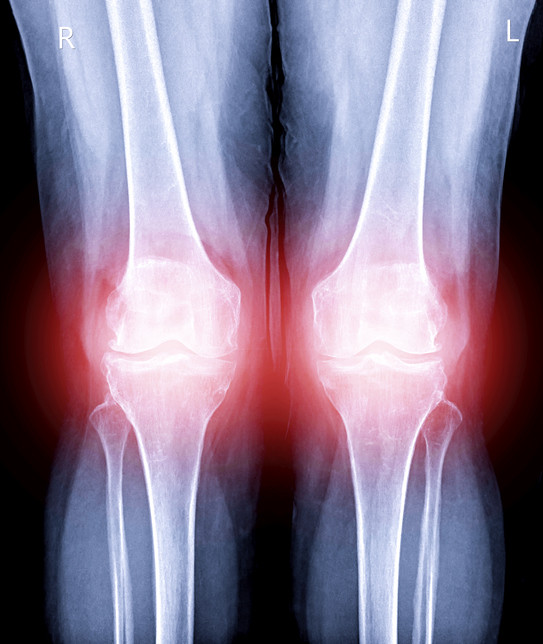

통증과 부기 동반하는 '통풍 초기증상'통풍이란 질병은 몸 속에 있는 요산이 제대로 배출되지 않고 축적돼 그로 인한 요산 결정이 발생해 발생하는 질병이다. 이러한 요산 결정은 관절이나 연골에서 염증을 유발해 통증을 불러온다. 통풍의 초기증상은 대부분 엄지발가락에 많이 나타난다. 걸을 때 엄지발가락에 아픔을 느끼다가 부기가 발생할 수 있다. 악화될수록 관절에 열감을 느끼고 붉게 변하거나 부기를 함께 느낄 수 있다. 증상이 심해지면 통증을 느끼는 부분이 점차 많아지고 아픈 정도가 강화된다. 통풍을 앓다가도 통증이 사라질 수 있지만 이를 통풍 질병 자체가 완전히 없어졌다고 여기면 안된다. 통풍을 방치하면 그로 인해 발생할 수 있는 다른 합병증을 유발할 수 있으므로 그에 맞는 빠른 치료를 받아야 한다.